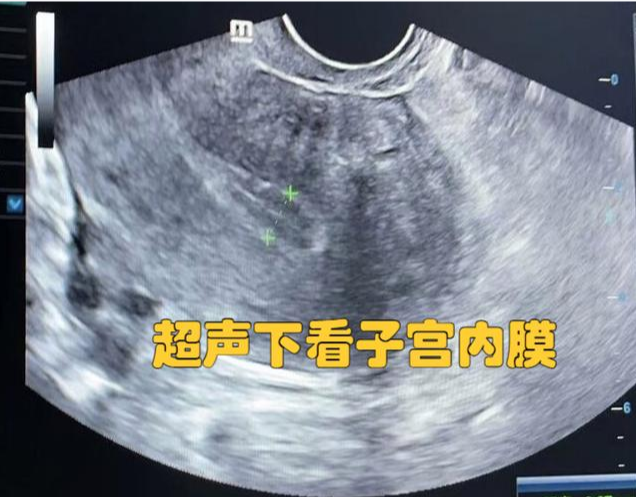

在试管婴儿治疗中,经过激素药物准备后,医生会通过阴道B超反复监测内膜情况。

·公认的“黄金标准”:通常认为,当子宫内膜厚度达到8-12毫米,并且形态为清晰的三线征+

(A型)时,是进行胚胎移植的最佳状态。这时的成功率最高。